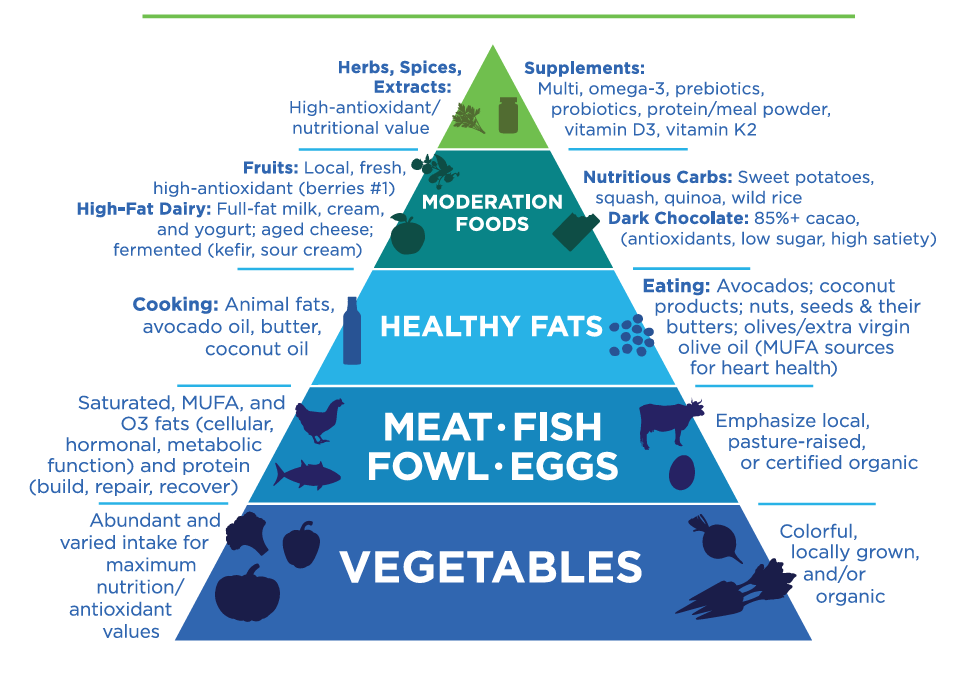

The Primal Approach: Reconnecting with Ancestral Health for Metabolic Wellness

As a health coach, I advocate for embracing an anthropologically inspired Primal lifestyle, drawing from principles rooted in our human evolutionary past. This approach proves beneficial in combating metabolic syndrome for several compelling reasons.

- Whole Foods Focus: The Primal lifestyle emphasizes whole, unprocessed foods such as meats, fish, vegetables, fruits, nuts, and seeds. These nutrient-dense foods provide essential vitamins, minerals, and fiber, promoting overall metabolic health.

- Low Processed Sugar and Carbohydrate Intake: The Primal approach limits processed sugars and refined carbohydrates, helping regulate blood sugar levels. Lowering the number of carbohydrates can reduce the risk of insulin resistance, a critical factor in metabolic syndrome.

- Balanced Macronutrient Intake: It encourages a balanced intake of macronutrients, including healthy fats, lean proteins, and carbohydrates from whole foods. This balance supports optimal metabolic function and energy production.

- Healthy Fat Emphasis: The Primal lifestyle includes healthy fats from avocados, olive oil, and nuts. These fats can improve lipid profiles, enhance satiety, and increase metabolic flexibility.

- Intermittent Fasting: Some Primal approaches incorporate intermittent fasting, a practice linked to improved insulin sensitivity, better blood sugar control, and enhanced fat metabolism.

- Physical Activity: The Primal lifestyle emphasizes regular physical activity, which is crucial for weight management, insulin sensitivity, and overall metabolic health.

- Reduced Inflammatory Foods: By minimizing or excluding processed foods, grains, and dairy, the Primal approach can help reduce inflammation, a key contributor to metabolic syndrome.

- Nutrient Density: Prioritizing nutrient-dense foods ensures the body receives essential nutrients, supporting various metabolic processes and overall well-being.

- Blood Sugar Regulation: The Primal lifestyle, focusing on whole foods and lower-glycemic options, contributes to better blood sugar regulation, reducing the risk of metabolic syndrome.

- Weight Management: Combining a Primal diet and lifestyle supports healthy weight management, addressing a fundamental aspect of metabolic syndrome.

Adopting a Primal lifestyle is involves dietary choices and encompasses broader aspects such as physical activity, sleep, and stress management. A holistic diet based on primal principles promotes metabolic resilience and overall well-being.